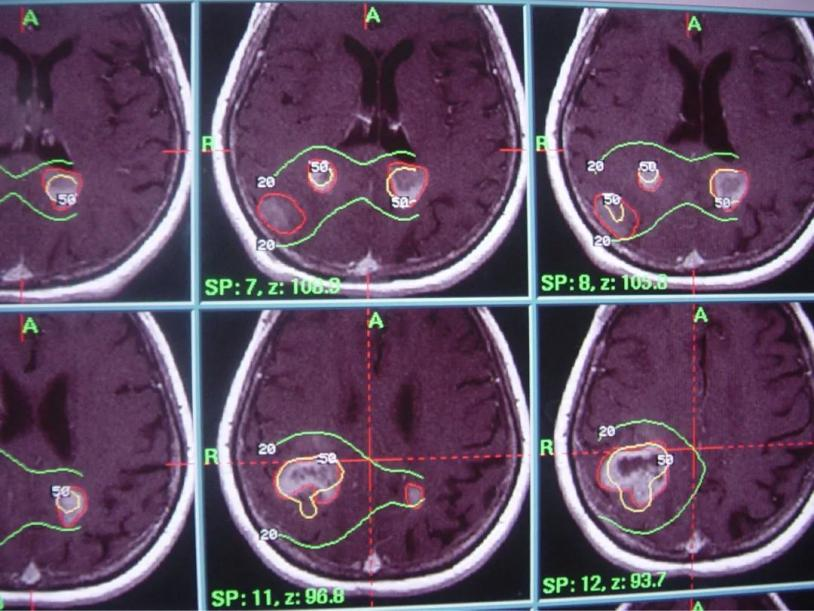

2) 病灶影像定位(MRI或者CT下)

伽马刀又称立体定向伽马射线放射治疗,是融立体定向技术和放射技术于一体,以治疗颅内疾病为主的立体定向放射外科治疗设备。其原理是将钴-60发出的伽马射线几何聚焦,集中射于病灶,一次性致死性的摧毁靶点内的组织,射线经过人体正常组织几乎无伤害,并且剂量锐减,相比其他治疗照射范围与正常组织间界限非常明显,边缘如刀割一样,人们形象称之为“伽玛刀”。

2. 采用旋转聚焦的手段,可以做到靶区剂量高,而周围正常组织受量较低,保护了正常的脑组织;